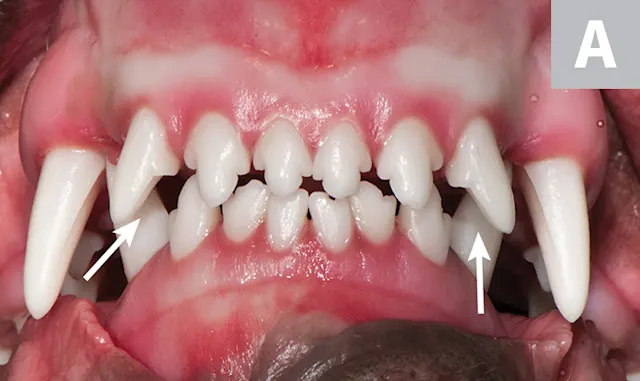

FIGURE 1A

Linguoversion of the mandibular canines (arrows) in a pitbull mix with traumatic ulceration.